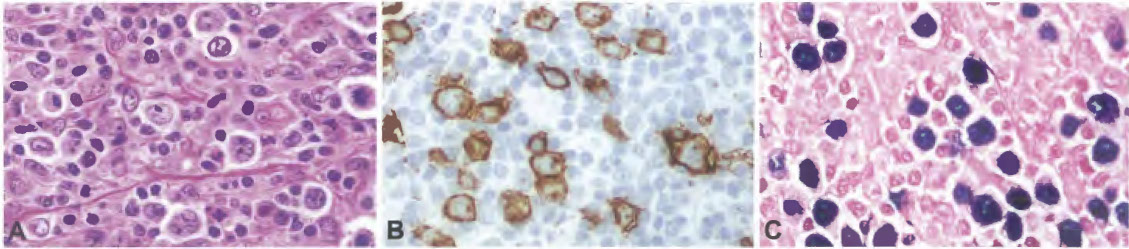

EBV-positive mucocutaneous ulcer

Nodular lymphocyte predominant Hodgkin lymphoma (NLPHL)

Classic Hodgkin Lymphoma (cHL)

- Nodular sclerosis classic Hodgkin lymphoma

- Mixed-cellularity classic Hodgkin lymphoma

- Lymphocyte-rich classic Hodgkin lymphoma

- Lymphocyte depleted classic Hodgkin lymphoma